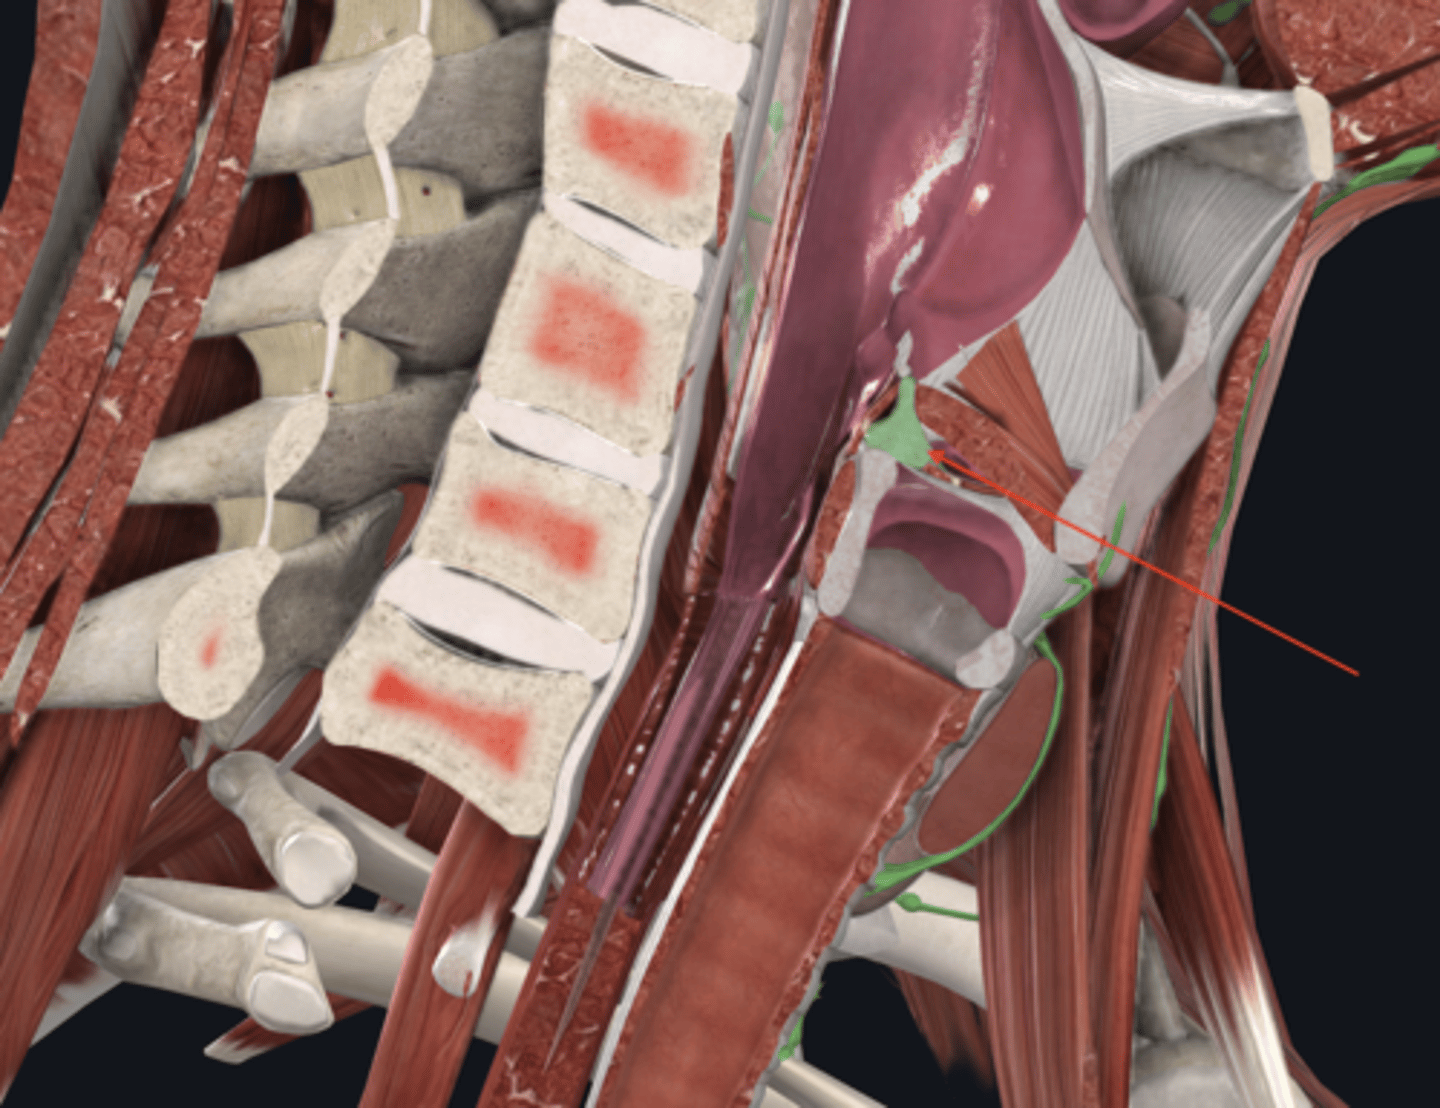

trachea

tracheal cartilages

annular ligament

right main bronchus

left main bronchus

lobar bronchi

terminal bronchi

diaphragm

anterior scalene

middle scalene

posterior scalene

sternocleidomastoid

intercostal muscles

pleural sac

serous membrane that surrounds the lungs and has a visceral and parietal layer